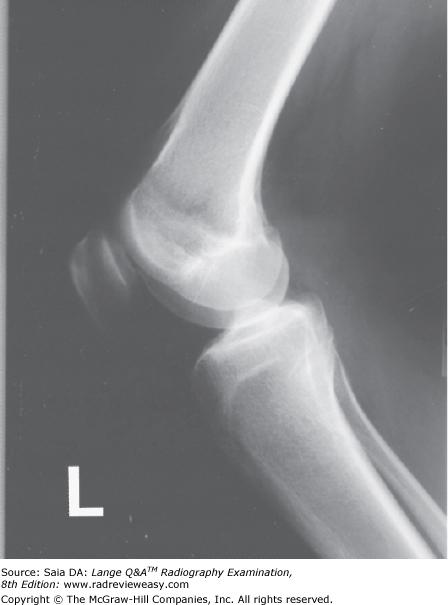

What is the name of the structure indicated as number 5 in Figure 7–7?

Olecranon fossa

In which of the following projections was the image in Figure 2–7 made?

medial oblique

Which of the following anatomic structures is indicated by the number 2 in Figure 2–7?

olecranon process